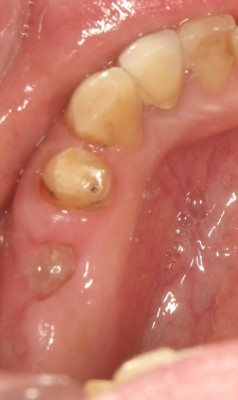

インプラントの術前・術後 Kさん